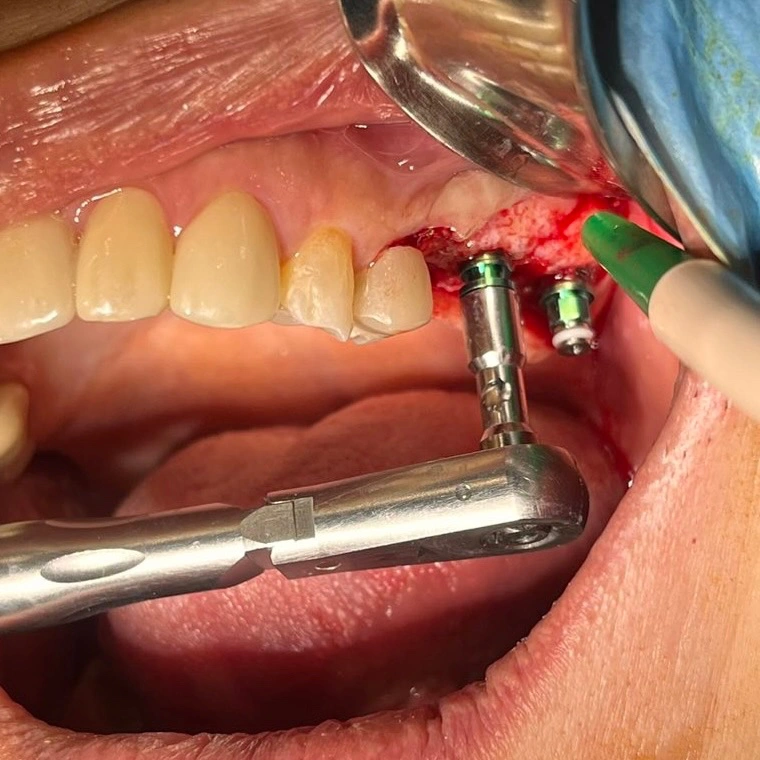

- Local anesthesia or Conscious Sedation for comfort

- Implants placed into jawbone via small incisions

- Bone grafting performed if needed

- Typical duration: 1–2 hours depending on complexity